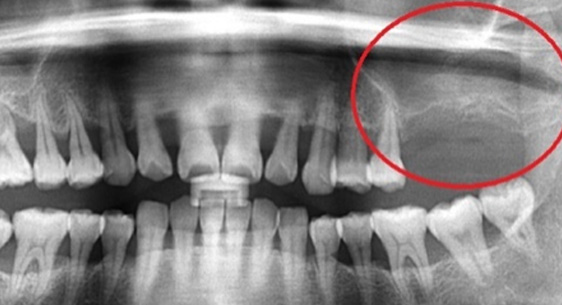

잇몸 염증으로 치조골 손실이 많은 상태

위 턱뼈는 아래턱뼈보다 얇고 코와 뺨 사이 빈 공간(상악동)이 있어서 임플란트를 식립할 경우 실패 가능성이 높아집니다.

상악동거상술이란 임플란트 수술방법을 시행할 때 노하우가 부족하면 임플란트 식립 후 임플란트가 빠져버리거나 입 천장 쪽에 구멍(천공)이 나는 부작용이

생기기 때문에 치과치료 중 가장 어려운 수술 중 하나 입니다.